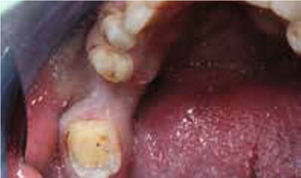

Bij het extraoraal onderzoek zie ik een lichte hypertrofie van de m. masseter. Intraoraal tref ik een ernstig versleten dentitie aan waarbij de slijtage niet passend bij de leeftijd kan worden genoemd (afbeelding 2-7 en tabel 1) .

Afb. 1

De heer H. bij de intake.

Occlusaal aanzicht van de onderkaak.

Afbeelding vergroten